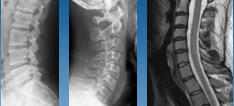

Mr Mark Sherwood - Orthopaedic and Spinal Surgeon BMedSc, MBChB (Otago, 1991), FRACS 2001 Mr Sherwood is an experienced orthopaedic surgeon who completed his advanced training in spinal surgery in New Zealand and Australia. He has been working as a specialist spinal surgeon for almost 25 years and has been a medical doctor for close to 35 years. He is an expert in the diagnosis and surgical treatment of adult spinal injuries and conditions including age-related degeneration, spinal deformity and tumours. He also treats scoliosis and complex spinal conditions in children. He performs surgeries at Wakefield Hospital and Southern Cross Hospital.  Mr Sherwood worked at Wellington Regional Hospital as a registrar and then as a consultant orthopaedic and spinal surgeon for 18 years. He is passionate about international charitable mission surgery. Over the years, he has developed strategic collegial relationships with spinal surgeon colleagues in Tel Aviv and Jerusalem, Israel.  He has done three mission trips with volunteer spinal surgeons to do scoliosis surgery at FOCOS Hospital in Ghana, Africa, being involved with the FOCOS orthopaedic programme. He has performed spine surgery in the pacific island of Tonga.